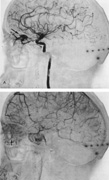

Vertebrobasilar System

Tortuous or redundant basilar arteries are not uncommon in the older age group. Occasionally, gross dilation or ectasia develops so that the basilar artery acts as a mass in the posterior fossa. This phenomenon produces signs of low-pressure hydrocephalus, cranial nerve palsies, and long tract and sensory signs and may even simulate a cerebellopontine angle tumor or tumor at the foramen magnum.58 It is possible to diagnose such lesions with CT59 or MRI60 but angiography is definitive (Fig. 6). The association of insidious multiple cranial nerve palsies and long tract signs referable to a brainstem level, in an elderly patient with evidence of atherosclerosis, should make fusiform basilar artery dilation a diagnostic consideration.

Fig. 6. Fusiform basilar dilation. A: Lateral projection vertebral arteriogram showing a widened basilar artery (arrow) projecting beyond level of dorsum sellae. B: Anteroposterior projection showing a widened and tortuous basilar artery.

As opposed to saccular basilar aneurysms, fusiform aneurysms tend to occur in the older age group (older than 60 years) and are found predominately in men.2,36 They are commonly associated with hypertension and atherosclerotic cardiovascular disease, and a notable association with abdominal aortic aneurysms also exists.